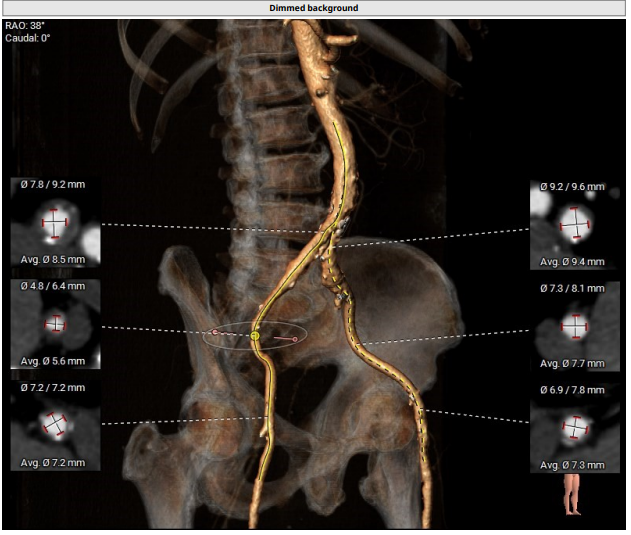

入路情况:主动脉弓部走行较平缓,可见少许钙化斑块。

主动脉弓部走行平缓,可见少许钙化斑块。主动脉弓部三根毛开口未见明显狭窄征象、未见发育变异。胸主动脉、腹主动脉走行较直,未见溃疡、钙化及非钙化斑块,管腔未见明显狭窄。双侧髂动脉-股动脉走形稍迂曲,可见少许钙化斑块,管腔未见明显狭窄。综合考虑,推荐右侧股动脉做为主入路。右侧股动脉穿刺水平管腔直径约为7.2mm,右侧股动脉分叉约在股骨头中部。

腹主动脉可见少许溃疡、钙化及非钙化斑块,管腔未见明显狭窄。双侧髂动脉-股动脉走形稍迂曲,可见少许钙化斑块,管腔未见明显狭窄。综合考虑,推荐右侧股动脉做为主入路。右侧股动脉穿刺水平管腔直径约为7.2mm,右侧股动脉分叉约在股骨头中部。